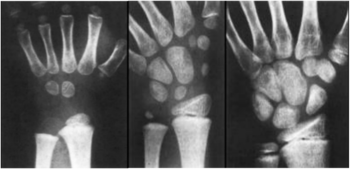

A középső csoport végén a gyermekek negyedének írásmozgás-koordinációja csupán az előkészítő szintet éri el. Nagycsoport végéig ez az arány 4 százalékra csökken. Az óvodában még nem szükséges annak feltárása, hogy esetükben fejlődésbeli fáziskésésről van szó, vagy fennáll a diszgráfia lehetősége. Az írásmozgás-koordináció spontán fejlődése kettő–öt évig tart, így alkalmankénti gyakorlás, esetleg rövidebb ideig tartó fejlesztőprogramok alkalmazása helyett három-négy éves segítő program kidolgozása és megvalósítása lenne célravezető. A kéz és az ujjak finommozgását igénylő játékos feladatok, tevékenységek mindennapi alkalmazása javasolt. Fontos, hogy a kiválasztott tevékenység során a gyermek a kéz három ujját is működtesse (a hüvelykujját, a mutatóujját és a középső ujját), és örömmel vesse bele magát a munkába. Az írásmozgás-koordináció direkt fejlesztése nem javasolt, inkább komplex tevékenységekbe ágyazva (Miskolcziné Radics, 2017). Fontos tudni, hogy a kéztő és az ujjpercek csontosodása erőteljes fejlődésnek indul óvodáskorban, a kézmozgások differenciáltabbá, összerendezettebbé válnak (9.1. ábra), ami az írástanulás alapját képezi (Danis et al., 2011).

9.1. ábra. A porcos elemek csontosodási folyamata: 1. év, 2. év, 12. év

Forrás: Dr. Kovács Magdolna előadása, Anatómiai Intézet, 2007. február 12.